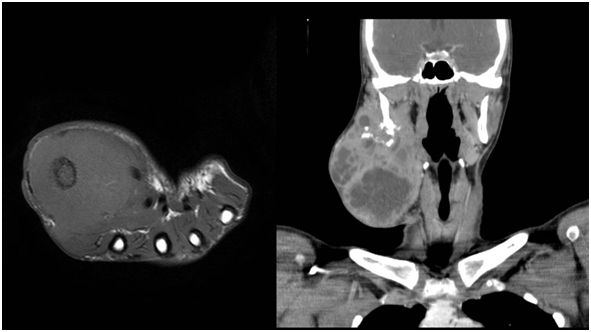

Figure 5 STIR coronal sequences of the pelvis, MRI images showing a heterogeneously hyperintense mass in the pelvis arising from the acetabulum.

Figure 6 MRI of the foot, sagittal STIR sequence showing a heterogeneous mass involving the fore and mid foot.

Figure 9 Contrast enhanced axial CT sections of abdomen showing a heterogeneous mass in the right para-spinal region.

Figure 10 Contrast enhanced axial CT sections of the thorax showing a heterogenous mass arising from the chest wall.